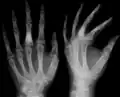

- X-ray showing calcified enchondromas localized in finger a 37-year-old patient affected with Ollier disease